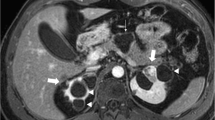

Beckwith–Wiedemann syndrome. Annual renal/bladder imaging follow-up in a 6-year-old boy with left kidney hydronephrosis evident since prenatal imaging. a, b Axial (a) and coronal (b) magnetic resonance urography images show a 1-cm lesion that is hypoechoic to renal cortex (arrows). Nephron-sparing surgery revealed histopathology with a mixture of nephrogenic rest and Wilms tumor without a capsule, indicative of an evolving Wilms tumor. Genetic consult identified macroglossia and hemihypertrophy and genetic testing showed hypermethylation of IC1, consistent with Beckwith–Wiedemann syndrome

Beckwith–Wiedemann syndrome stands as the prototype predisposition syndrome for Wilms tumor (Fig. 1). It affects at least 1 in 11,000 children and is characterized by overgrowth, macroglossia, omphalocele and hemihyperplasia, with predisposition for Wilms tumor and hepatoblastoma. Clinical features are attributed to genetic and epigenetic changes in chromosome 11p15. Paternal disomy of 11 (UPD11) and methylation at imprinting center 1 (IC1) confer a high risk of tumor (up to about 30%) [20, 21]. Low-risk (epi)genotypes include CDKN1C variants and loss of methylation at IC2. The former also confers a neuroblastoma predisposition. Idiopathic hemihyperplasia does not have additional features of Beckwith–Wiedemann syndrome but carries an elevated risk of Wilms tumor. It is thought to be a forme fruste of an “11p overgrowth” spectrum.

Current surveillance recommendations in the United States do not differentiate high- from low-risk genotypes for Beckwith–Wiedemann syndrome. Recommendations are instituted based on estimated risk of cancer incidence of at least 1% and these are likely to evolve to incorporate genotypic distinctions as they are further characterized. Based on an epidemiologic analysis, imaging surveillance recommendations for Wilms tumor consist of renal US every 3 months through the 7th birthday; imaging surveillance for hepatoblastoma adds abdominal US (which can supplant the renal US) every 3 months through the 4th birthday, with monitoring of alpha fetoprotein (AFP) levels. Abdominal MRI is recommended for further characterization of any lesion seen on US, or if serum AFP increases over two successive tests 6 weeks apart [19].